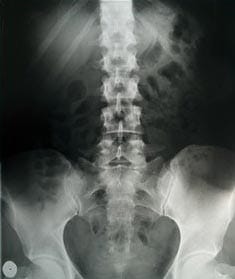

At the ER, there is a bit of a wait. When John is finally seen, a full assessment is conducted and x-rays are taken of his back. Luckily his x-rays are normal, and there is no sign of fracture. The source of his pain is determined to be a pulled muscle.

Click To Enlarge